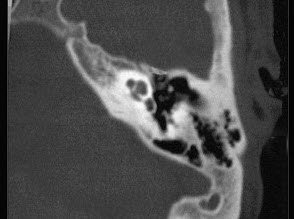

一男性患者,持续左耳流脓10年,检查示左侧35dB下降的传导性耳聋,如图分别为他的鼓膜外观和颞骨CT检查,可诊断为()。

A:慢性化脓性中耳炎单纯型

B:慢性化脓性中耳炎骨疡型

C:慢性化脓性中耳炎胆脂瘤型

D:急性中耳炎

E:以上都不是